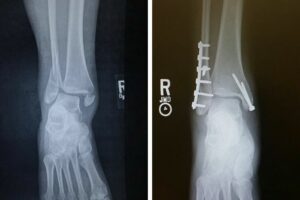

Surgical Treatments

- Internal fixation with plates, screws, or rods

- Minimally invasive fracture repair when possible

- Reconstruction for joint-involving fractures

- Surgery for pelvic or multi-bone fractures

- Revision procedures for delayed or non-healing fractures

What is ORIF and when is it used?

ORIF (Open Reduction and Internal Fixation) is a surgical technique used to realign and stabilize complex fractures using plates, screws, or rods.